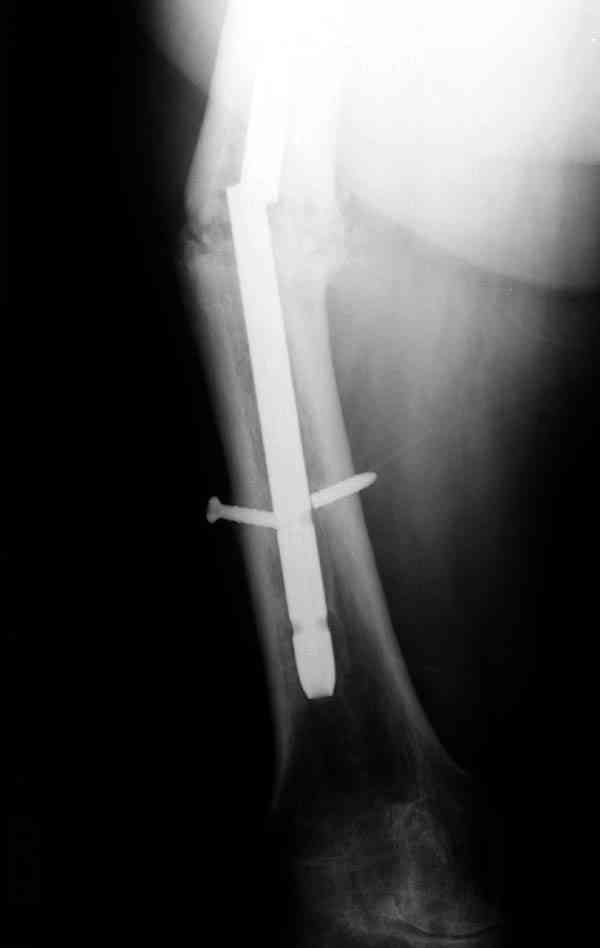

Сросшаяся малоберцовая как распорка привела к образованию ложного

сустава. В таких случаях удаляем сломанный штифт и проводим

стимуляцию ложного сустава рассверливанием. Рассверливание канала

создает стимуляцию на месте ложного сустава, и динамический вариант

блокировки штифта с большим диаметром создаст стабильность. Ранняя

нагрузка после остеотомии малоберцовой приведет к сращению ложного

сустава.